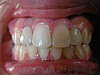

Le cas ci-dessus présente une adolescente ayant les 2 incisives latérales supérieures manquantes (absence congénitale/anodontie).

Après consultation avec le dentiste généraliste, il fût décidé d’ouvrir les espaces des latérales manquantes et de les faire remplacer prothétiquement après le traitement d’orthodontie effectué avec des multibagues.